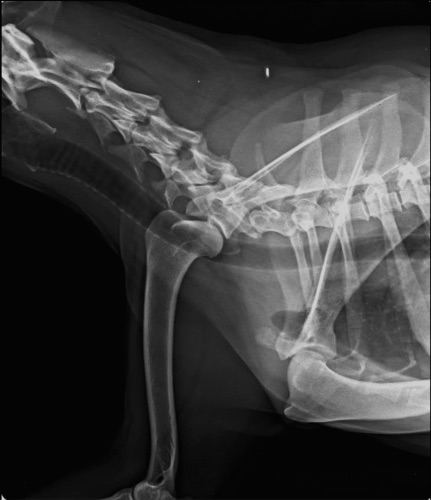

La locomotion est objectivée avec les différents paramètres mesurés à l’aide de l’outil Tendiboots™ Canine. Des examens radiographiques et échographiques ont également été effectués sur Kara.

![]() |